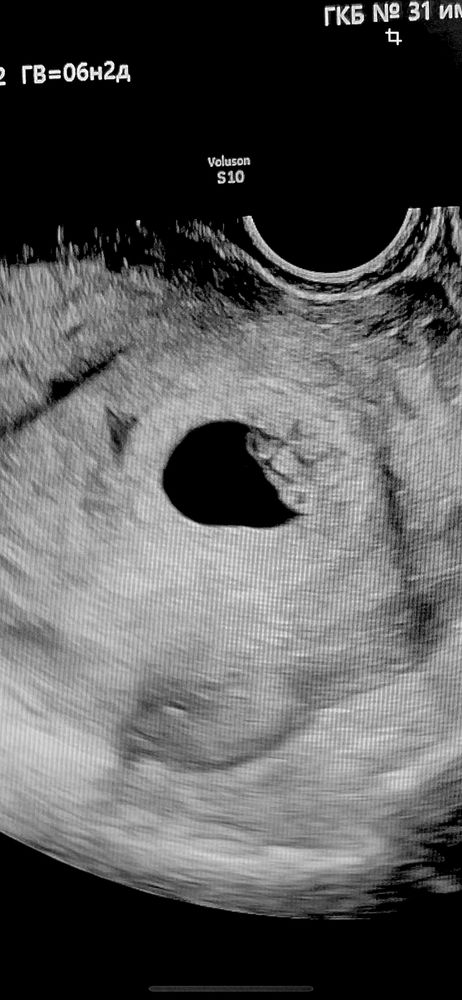

Мальчик

ИЛИОНА Диагностик Экстрасенс , как вы поняли что это мальчик?)